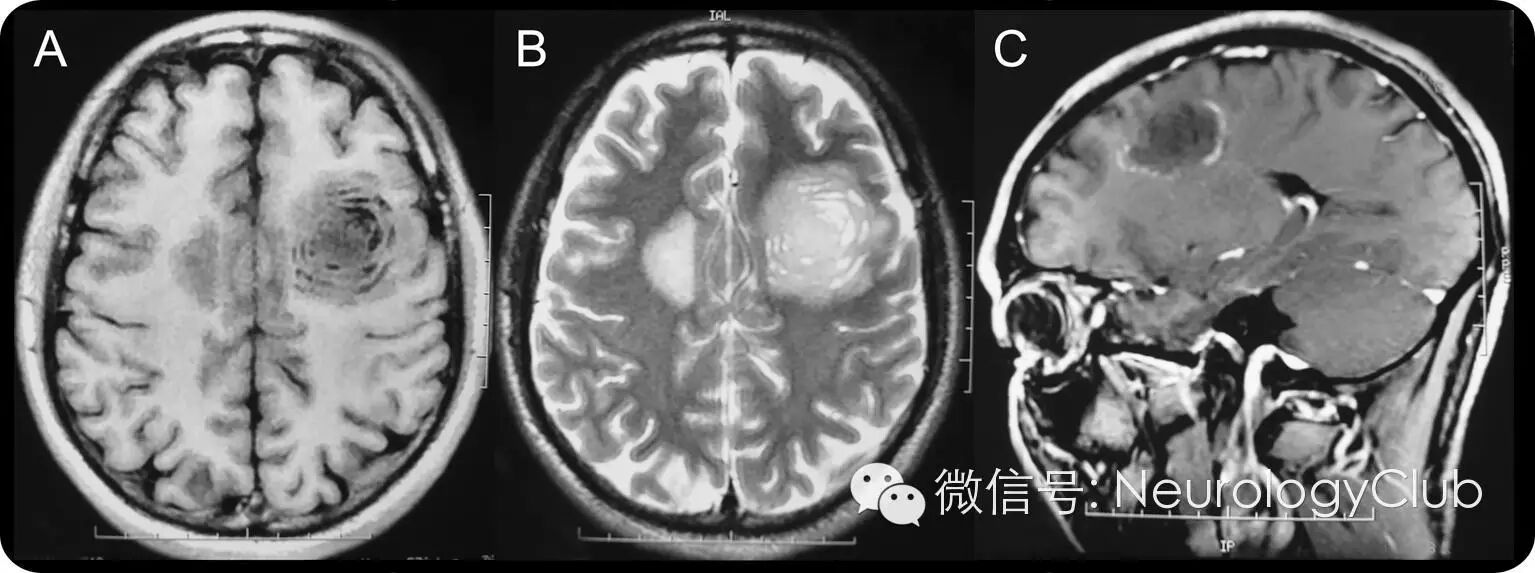

42岁男性,表现为亚急性起病的右侧轻偏瘫和轻度认知功能缺损,病前30天曾口服600mg左旋咪唑驱蛔虫。头颅MRI可见双侧额叶白质2处不规则病灶。左侧较大者为同心圆样(图A、B),注射对比剂后,呈环形强化(图C)。患者诊断为左旋咪唑诱发的脑白质病,影像学上的改变类似Baló病(同心圆硬化)。患者接受大剂量静脉激素治疗。症状在3月内改善,复查MRI提示病灶较前缩小。

(A:T1WI;B:T2WI;C:增强)